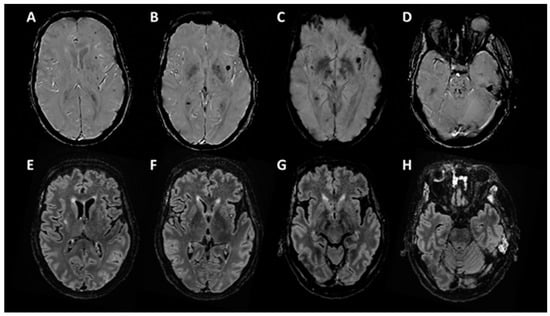

3.2.3. Brain Imagery